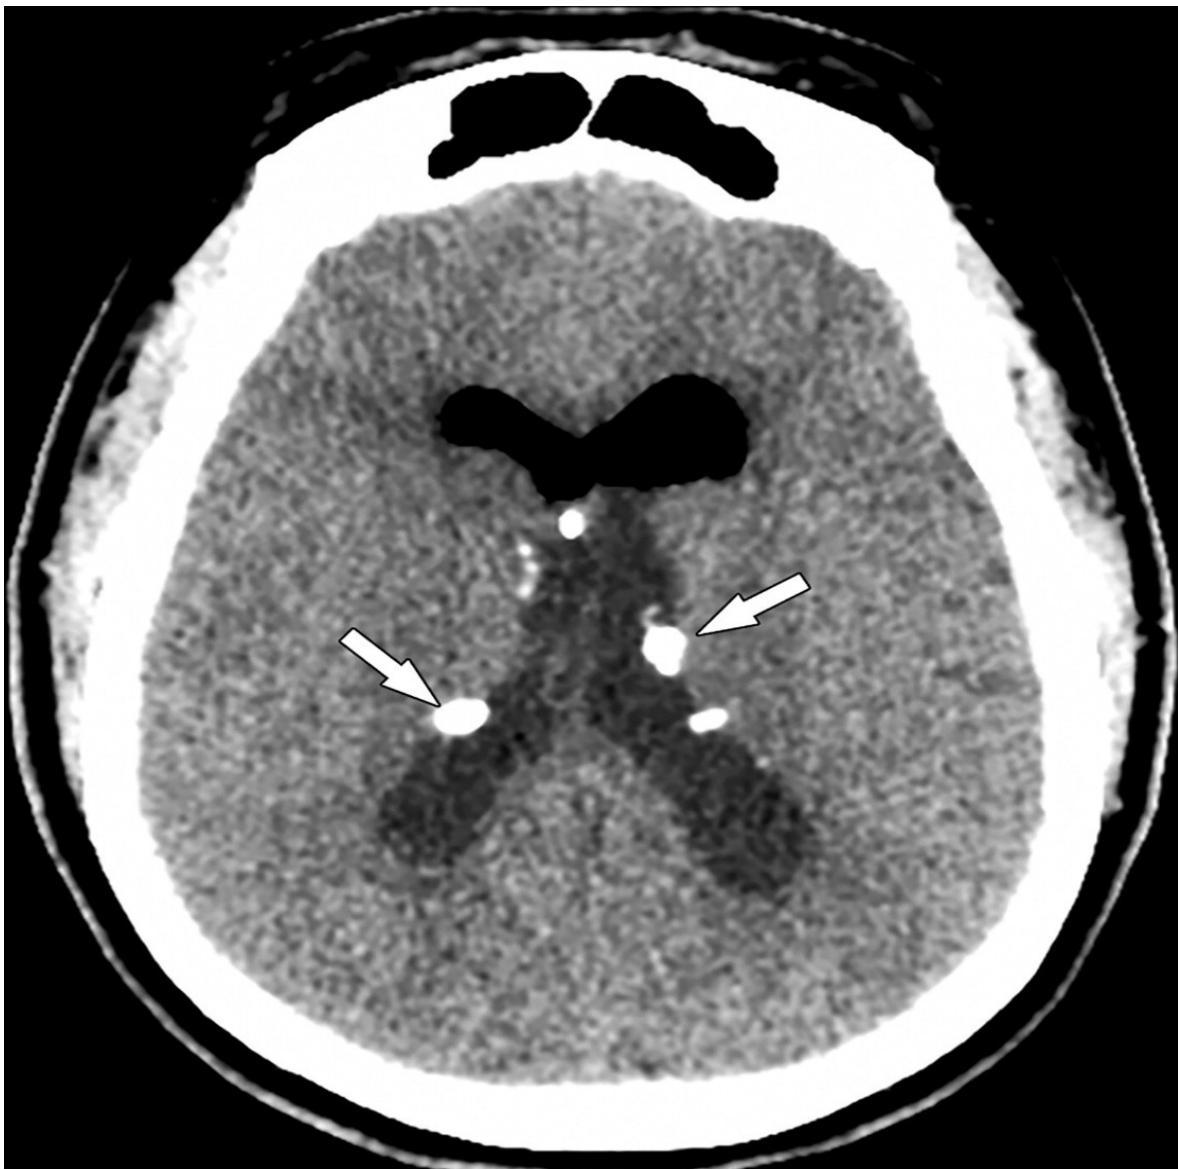

- Subependymal Nodules: Calcified nodules adjacent to lateral ventricles (Hamartomas).

Subependymal calcification: